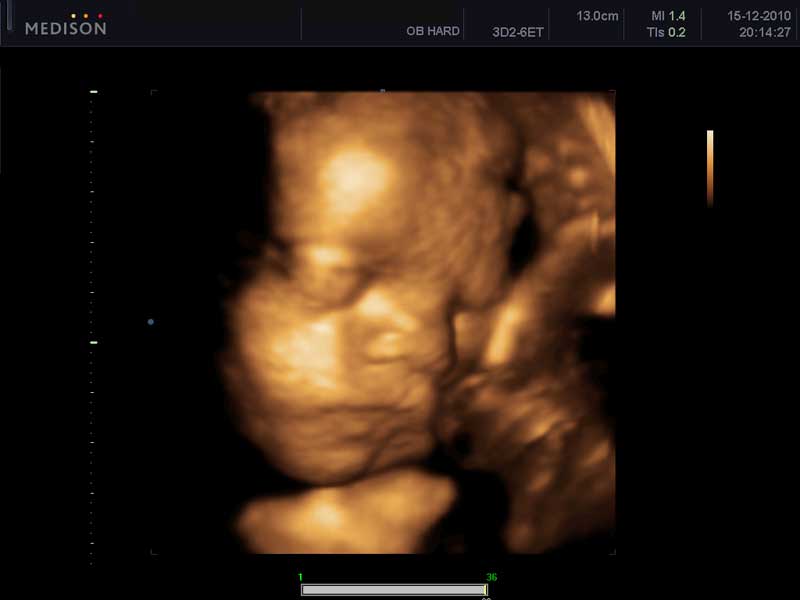

Στον 3ο μήνα και συγκεκριμένα μεταξύ 11ης και 14ης εβδομάδας κυήσεως πραγματοποιείται το υπερηχογράφημα αυχενικής διαφάνειας, στο οποίο μετράται το πάχος του υγρού που βρίσκεται κάτω από το δέρμα στον αυχένα του εμβρύου.

Αν αυτό βρεθεί αυξημένο, τότε υπάρχει αυξημένη πιθανότητα το έμβρυο να πάσχει από σύνδρομο Down. Η πιθανότητα είναι μεγαλύτερη σε γυναίκες μεγαλύτερης ηλικίας. Η ευαισθησία του υπερηχογραφήματος για την ανίχνευση του συνδρόμου Down είναι περίπου 80%. Σε συνδυασμό ,τώρα, με τον προσδιορισμό στο αίμα της εγκύου γυναίκας δύο πρωτεϊνών, του PAPP-Α και της ελεύθερης β χοριακής γοναδοτροπίνης καταφέρνουμε να ανεβάσουμε την ευαισθησία της μεθόδου ανιχνεύσεως εμβρύων με Σ.Down στο 90%…